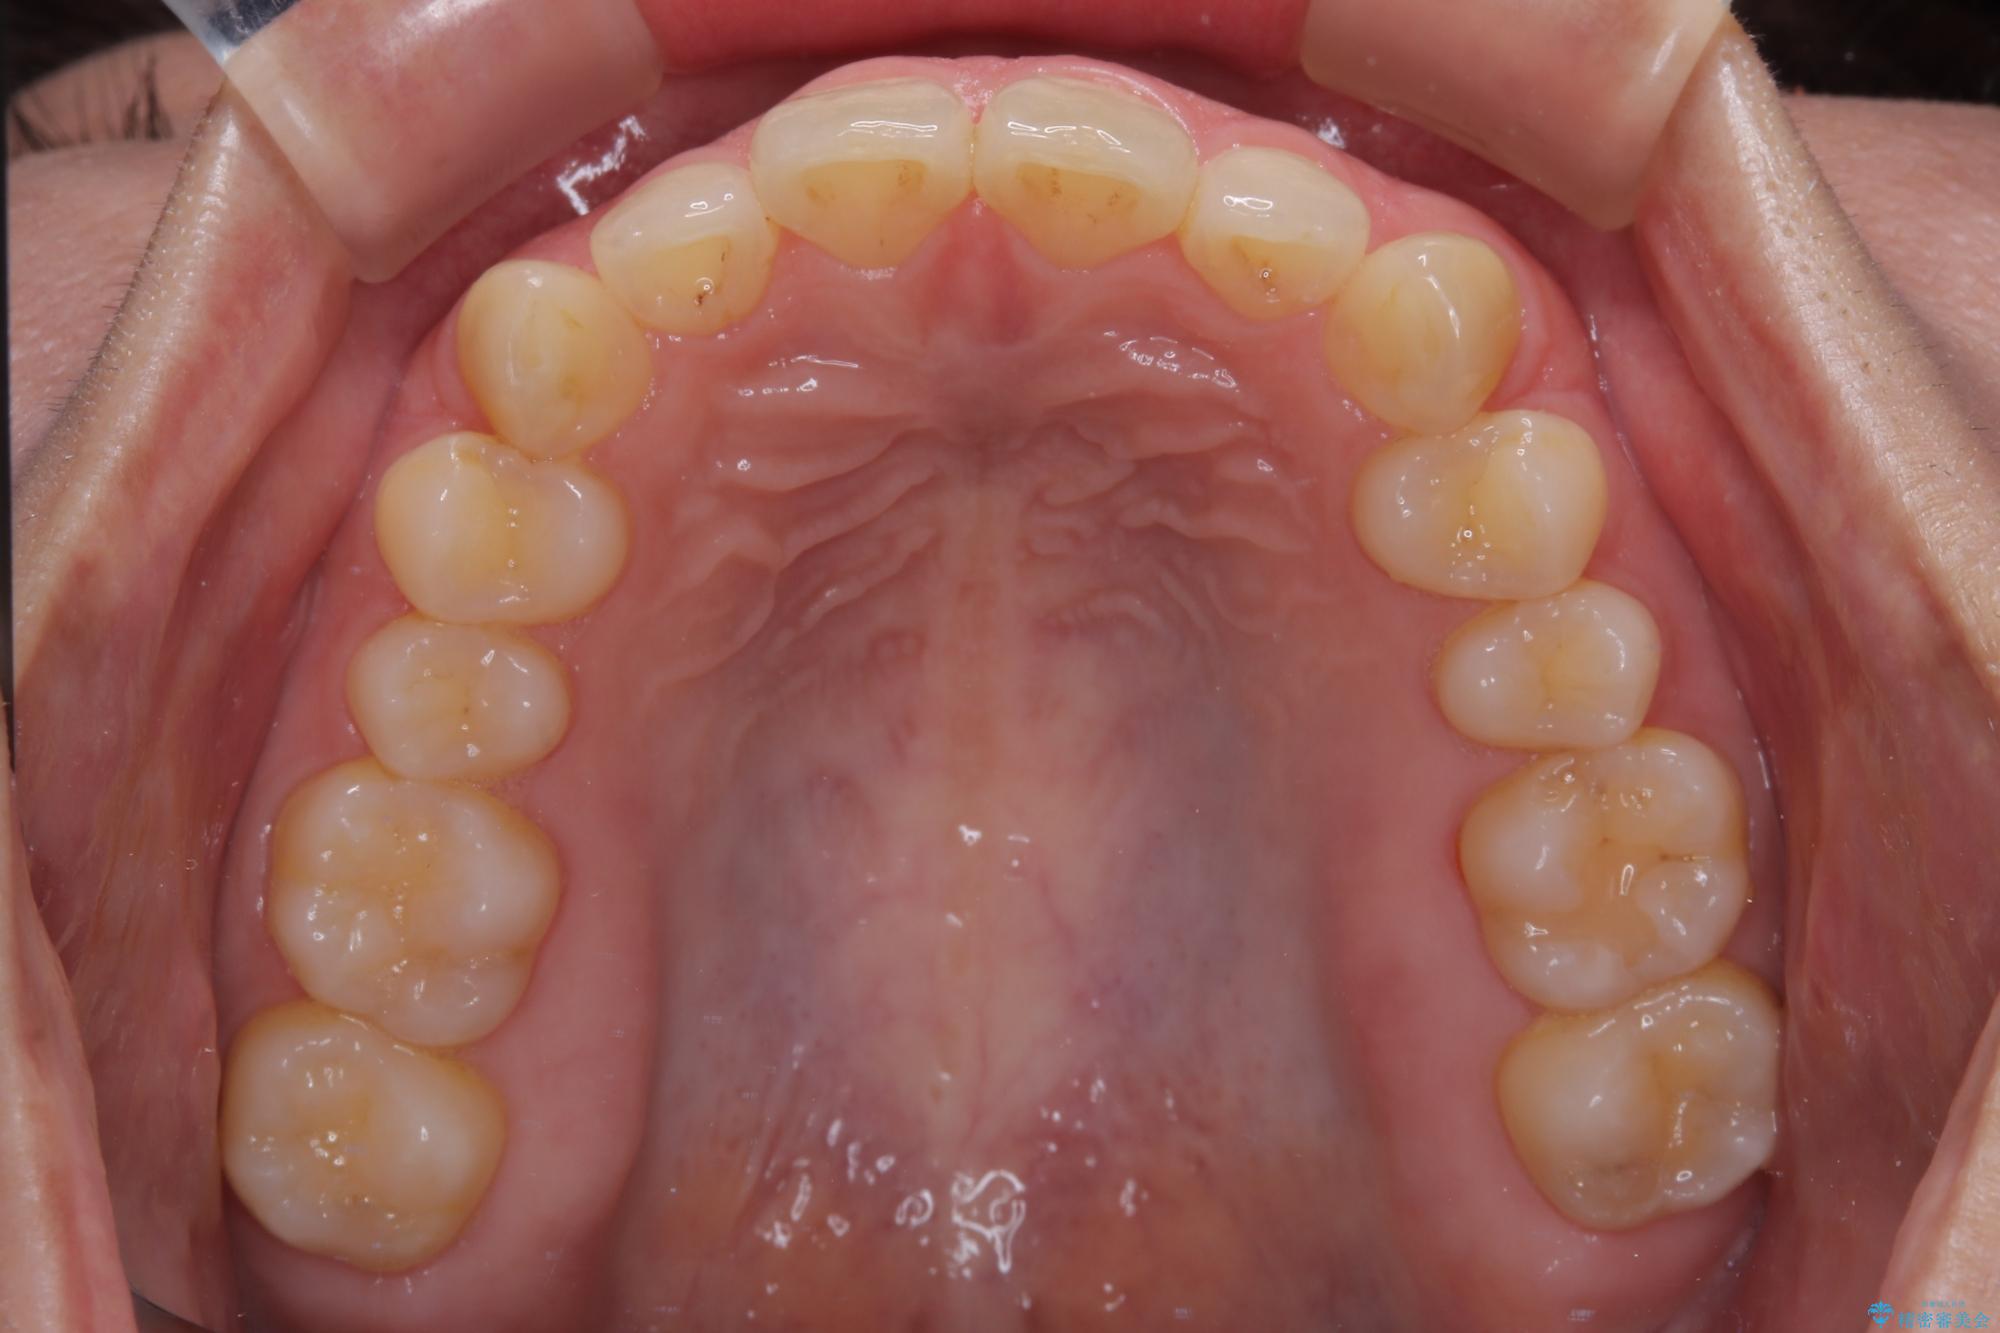

隠れた前歯が気になる ディープバイトのワイヤー矯正治療

- 下顎前歯が完全に隠れてしまっていることを気にして来院された患者様です。

下顎の臼歯が手前に傾斜していることで咬み合わせが深くなってしまい、下顎前歯が見えないほどに上顎前歯が覆い被さっている状態でした。

下顎臼歯を起き上がらせるためにユーティリティーアーチを使用し、一気に深い咬み合わせを改善することができました。